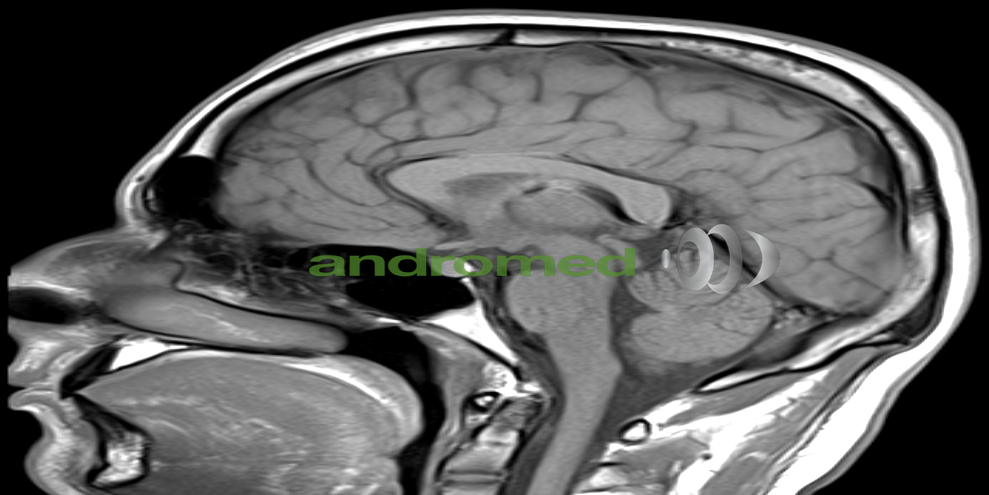

Diagnose im Bild: MRT-Diashow

1. Neurologie: Die Magnetresonanztomographie (MRT) spielt eine zentrale Rolle bei der Diagnose und Überwachung neurologischer Erkrankungen. Sie ermöglicht die detaillierte Darstellung von Gehirnstrukturen, die Identifizierung von Tumoren, die Bewertung von Blutungen, die Erkennung von Entzündungen sowie die Beurteilung von neurodegenerativen Erkrankungen wie Alzheimer und Parkinson.